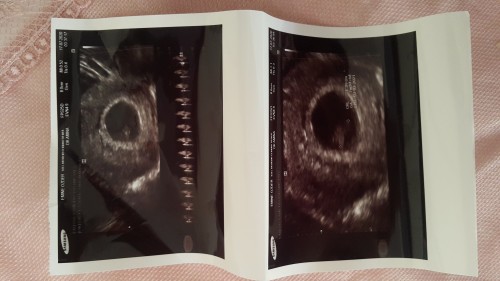

CİNSİYET NEDİR SİZCE ANNELER TAHMİNDE BULUNALIM

7 haftalık hamilelikte ciddi ciddi.bunu mu sordunuz geç kalmışsınız sormaya direk yumurta döllenme döllenmez sorsaydınız daha net olurduk :) tövbe estağfurullah  ... 22 haftaya kadar doktorlar bile sallıyor tam detaylı da belli oluyor

6 7 haftalık gibi duruyo daha çok küçük ayrıca küçük olmasa bile cinsiyeti biken birinin çıkacagını sanmıyorum :)

Anlıyorum heyecanlısin ama bir noktanın cinsiyetini nerden bilelim doktorlar ultrasonla bile en erken 12.haftada görüyor bazen son haftalarda bile göremeyen var. İyi ben şansımı kızdan yana kullanıyorum. Bence kız :)

Kız srn hac ayliksin bebek yokki bizimle dalgamı geçiyorsun

Kalp atışı bile yeni oluşmutur sen cinsiyet derdindesin. Önemli olan sağlıkla kucağına alman değil mi?